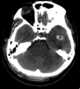

Cerebral contusion

Cerebral contusion, Latin contusio cerebri, a form of traumatic brain injury, is a bruise of the brain tissue. Like bruises in other tissues, cerebral contusion can be associated with multiple microhemorrhages, small blood vessel leaks into brain tissue. [Source: Wikipedia ]